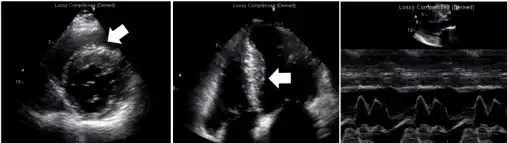

Echocardiogram exam shows left atrial enlargement (asymmetrical septal hypertrophy without left ventricle (LV) outflow tract obstruction, restrictive filling pattern, normal LV systolic function)[6]_(cropped).jpg.webp)

LAE is suggested by an electrocardiogram (ECG) that has a pronounced notch in the P wave.[8] However, if atrial fibrillation is present, a P wave would not be present.[9] In any case, LAE can be diagnosed and measured using an echocardiogram (ECHO) by measuring the left atrial volume (LAVI).